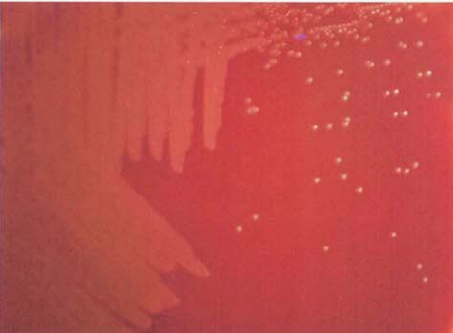

(二) 绿色气球菌培养特性

在血琼脂平板上35℃培养18~24h,形成圆形、凸起、针尖样大小小菌落,草绿色溶血环不明显,48h后菌落增大至1 mm,灰白色,草绿色溶血环明显(图 2),肉汤培养24h后呈均匀浑浊生长。

图 2绿色气球菌在血琼脂平板上的菌落特征(48h)